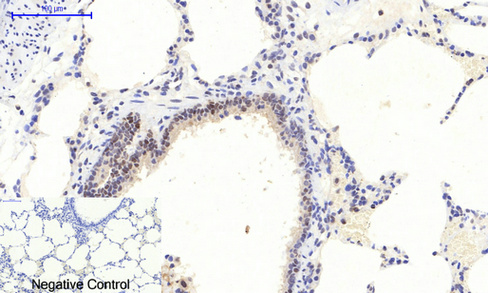

| IHC | 1/50-1/100 | Human,Mouse,Rat |

This phospho-specific antibody recognizes ERK1/2 only when phosphorylated at these residues, enabling researchers to distinguish active from inactive ERK1/2. It is commonly employed in techniques like Western blotting, immunofluorescence, and flow cytometry to study MAPK pathway activation in response to stimuli or inhibitors. Applications range from cancer research (e.g., assessing oncogenic signaling) to drug discovery (e.g., evaluating kinase inhibitor efficacy). Validation often includes testing in stimulated vs. unstimulated cells or tissues, with specificity confirmed using phosphorylation-blocking peptides or siRNA knockdown. Proper controls are essential, as cross-reactivity with other phosphorylated kinases or nonspecific binding can occur. Its utility in both basic research and translational studies underscores its importance in understanding cellular signaling dynamics.